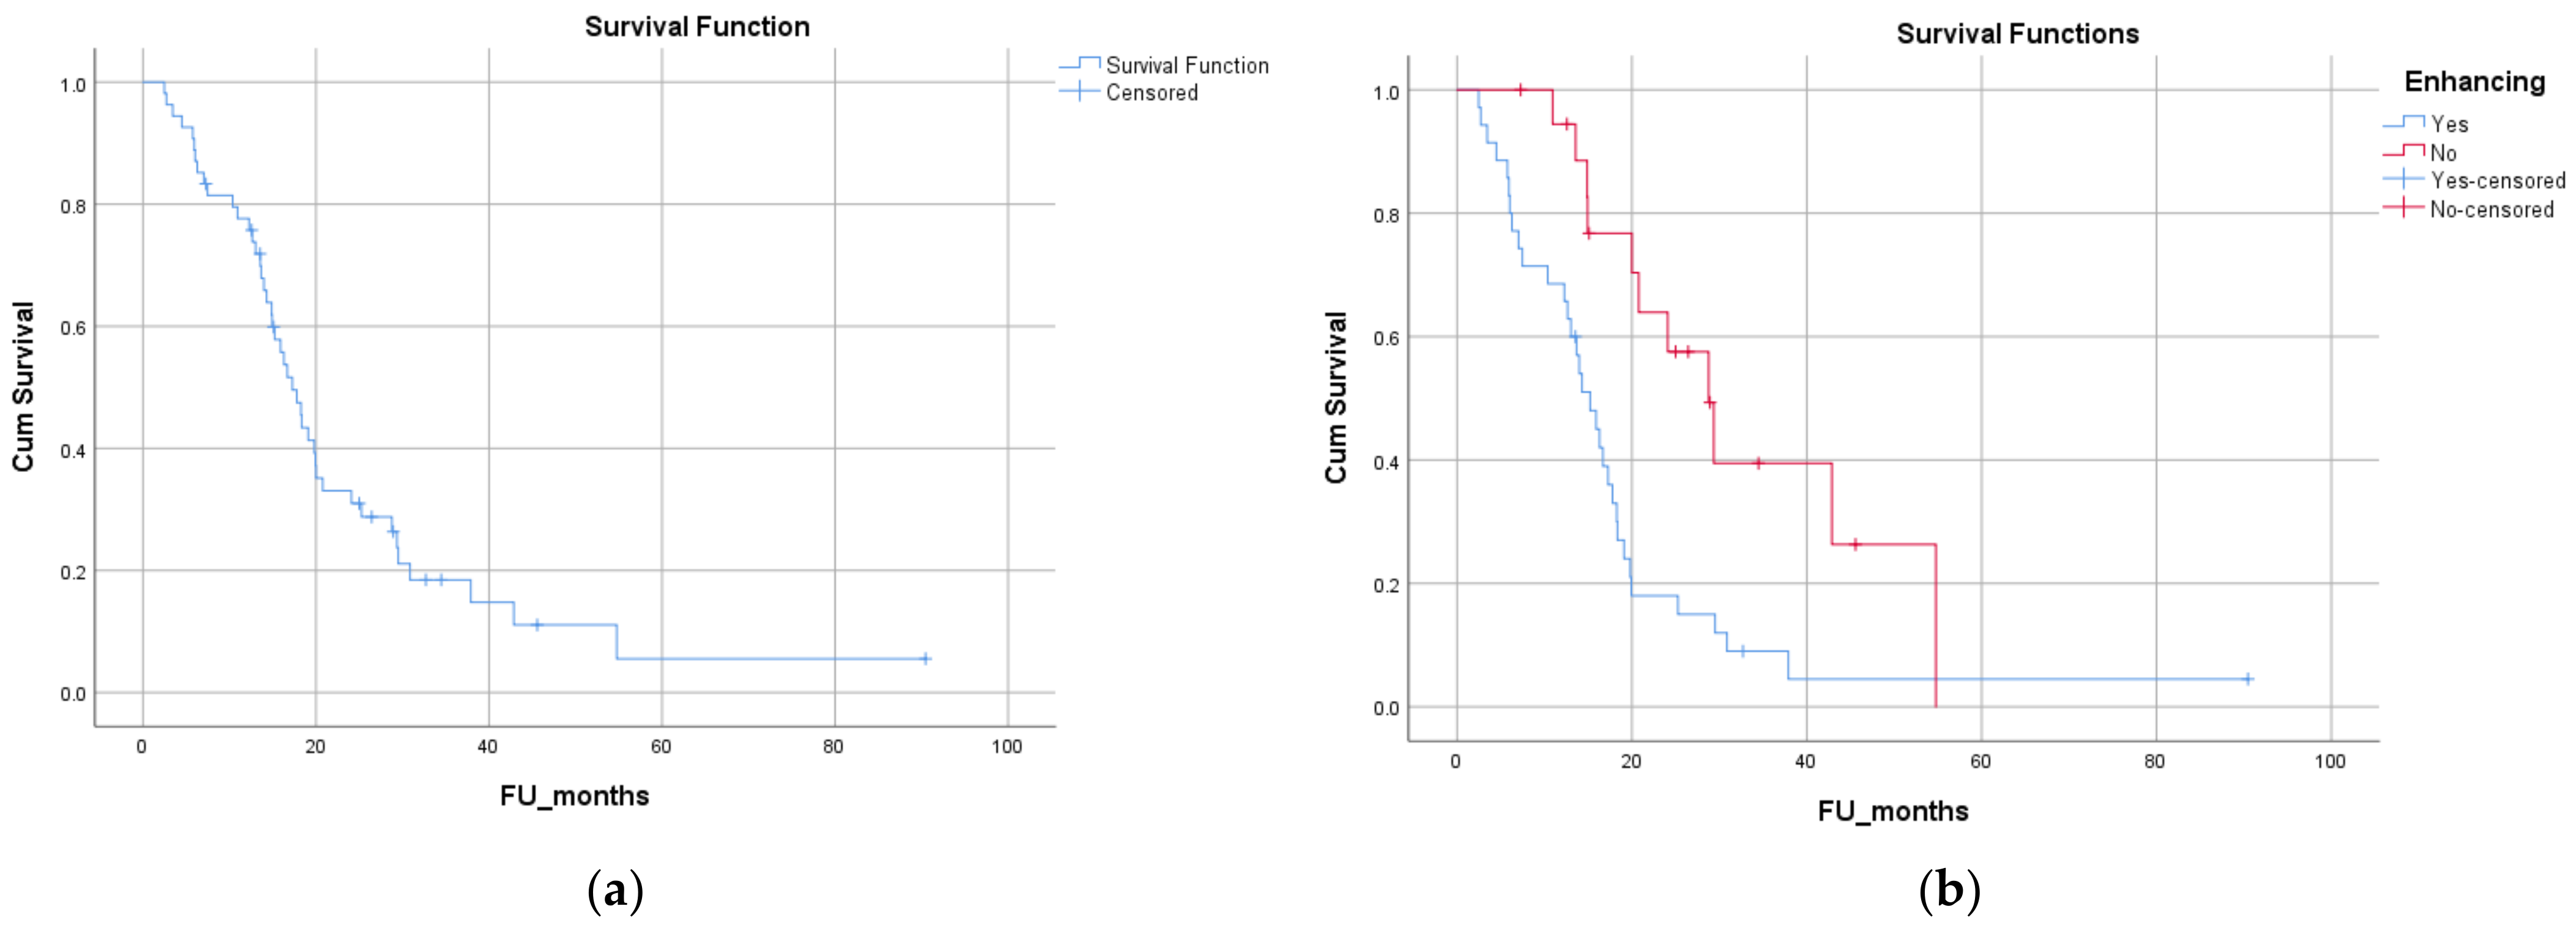

3.5. Survival Analysis

| Test Variable | Overall Survival [Median (CI)] | p-Value |

|---|---|---|

| Age at diagnosis (dichotomized at median—≤57 years vs. >57) | 20 (12.5 to 27.5) vs. 14 (9.8 to 18.8) months | p = 0.013 |

| Sex (female vs. male) | 17.3 (14.5 to 20) vs. 17.8 (12.3 to 23.2) months | p = 0.36 |

| Performance status (0 vs. 1 vs. 2) | 24 (0 to 60) vs. 18.3 (14 to 22.6) vs. 14.3 (0.7 to 27.8) months | p = 0.004 |

| Contrast enhancement on diagnostic MRI (present vs. absent) | 15.2 (12.1 to 18.3) vs. 28.8 (21.3 to 36.2) months | p = 0.003 |

| Location of the lesion on MRI (superficial vs. deep) | 18.3 (15.3 to 21.2) vs. 14.9 (12.7 to 17) months | p = 0.32 |

| Pattern of gadolinium enhancement (solid/patchy versus rim-enhancing with central necrosis) | 15.9 (12.5 to 19.3) vs. 14 (11.7 to 16.2) months | p = 0.57 |

| Pre-operative tumor volume on MRI (dichotomized at median—66.5 cc) | 20 (15.6 to 24.2) vs. 15 (12.3 to 17.6) months | p = 0.20 |

| ADC value (dichotomized at median—1.45) | 15.2 (11.4 to 19) vs. 19.8 (17.3 to 22.3) months | p = 0.43 |

| Type of surgery (biopsy vs. maximal safe resection) | 17.8 (15.5 to 20) vs. 14 (11.3 to 16.6) months | p = 0.91 |

| Complete resection vs. incomplete resection | 14.9 (7 to 22.9) vs. 17.3 (14.5 to 20) months | p = 0.28 |

| Time to surgery (from diagnostic MRI—<1 week vs. >1 week) | 15.2 (12.2 vs. 18.2) 18.3 (15 to 21.5) | p = 0.72 |

| Radical vs. palliative radiotherapy | 18.2 (14.2 to 22.16) vs. 16 (12.7 to 19.19) months | p = 0.20 |

| Dose of radiation (high dose vs. low dose) | 18.2 (14.2 to 22.16) vs. 16 (12.7 to 19.19) months | p = 0.20 |

| Concurrent chemotherapy | 19.8 (15.7 to 23.9) vs. 16 (11.9 to 19.9) months | p = 0.39 |

| MGMT status (methylated vs. unmethylated) | 16.67 (13.2 to 20.14) vs. 18.3 (12 to 24.65) months | p = 0.40 |